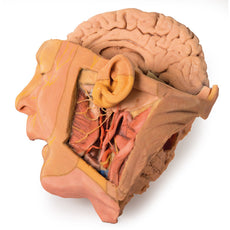

The head and neck of the specimen provides views of both superficial and deep structures in the region. The calotte has been removed ~2cm superior to the orbits to expose the brain in relation to the endocranial cavity. The transverse section through the cerebrum demonstrates the relation of the grey matter cortex to the white matter medulla, as well as the lateral ventricles with a small amount of choroid plexus visible in the base of both spaces. The skin and superficial fascia on the right side has been retained and false-coloured to display the angiosomes of the face and posterior neck. On the left side, the superficial tissues have been dissected to expose the muscles of facial expression, muscles of mastication, and deeper structures of the infratemporal fossa including the lingual nerve, terminal branches of the external carotid artery into the superficial temporal and maxillary arteries.

The head and neck of the specimen provides views of both superficial and deep structures in the region. The calotte has been removed ~2cm superior to the orbits to expose the brain in relation to the endocranial cavity. The transverse section through the cerebrum demonstrates the relation of the grey matter cortex to the white matter medulla, as well as the lateral ventricles with a small amount of choroid plexus visible in the base of both spaces. The skin and superficial fascia on the right side has been retained and false-coloured to display the angiosomes of the face and posterior neck. On the left side, the superficial tissues have been dissected to expose the muscles of facial expression, muscles of mastication, and deeper structures of the infratemporal fossa including the lingual nerve, terminal branches of the external carotid artery into the superficial temporal and maxillary arteries.